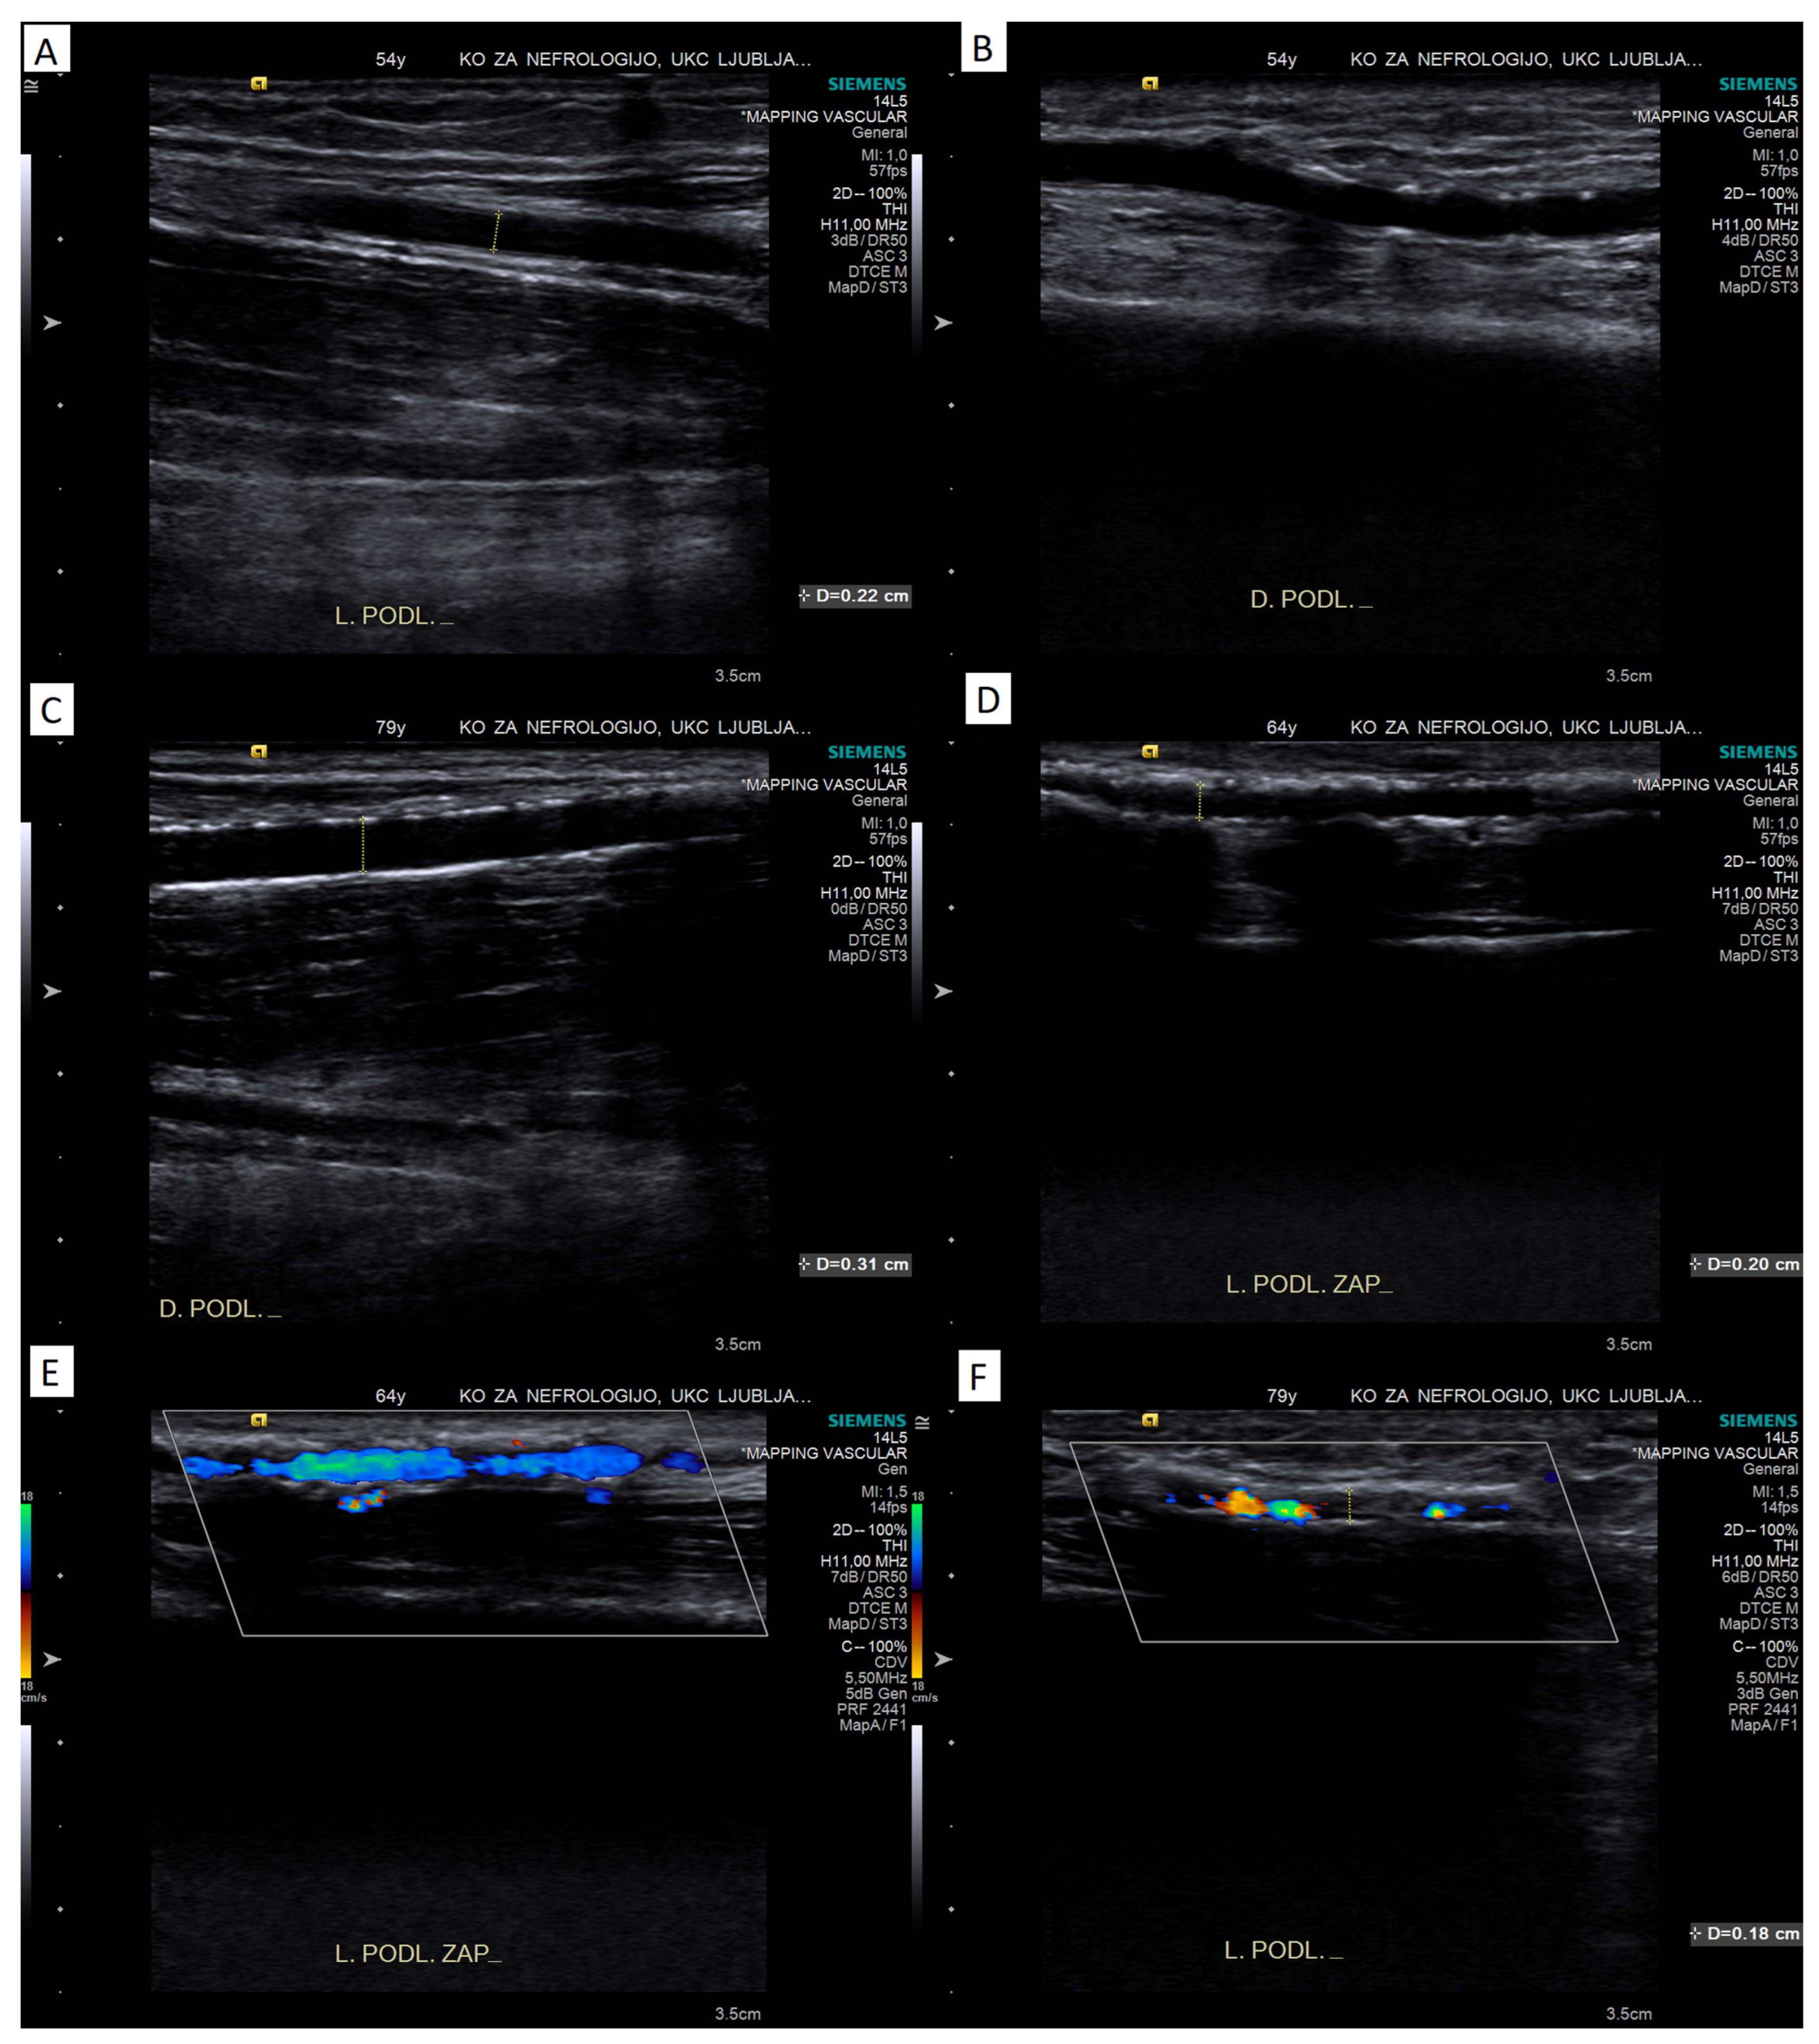

4.1.3. B-Mode Ultrasound

4.1.4. Compressibility of the Artery

4.1.5. Color Doppler Assessment